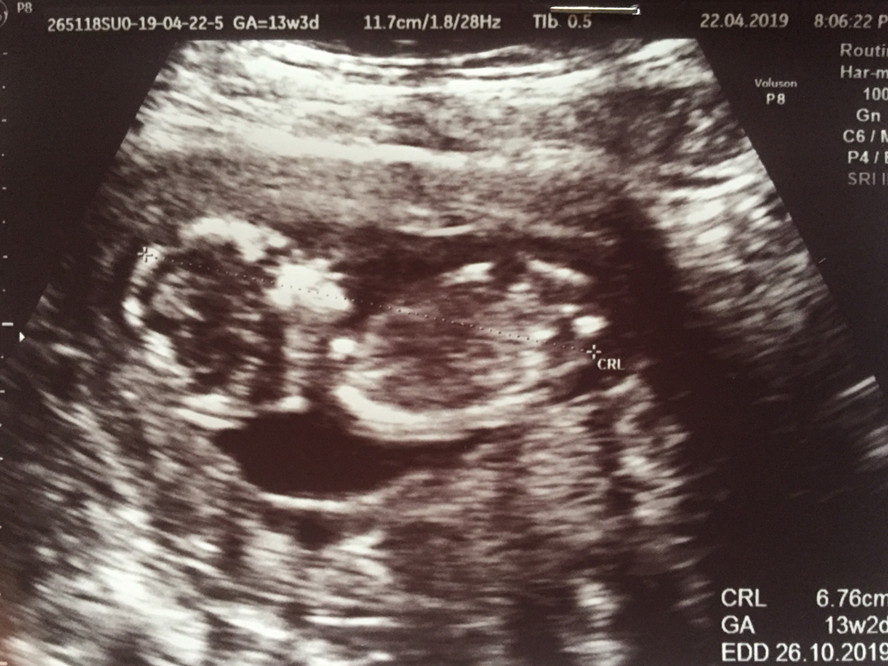

13wค่ะ